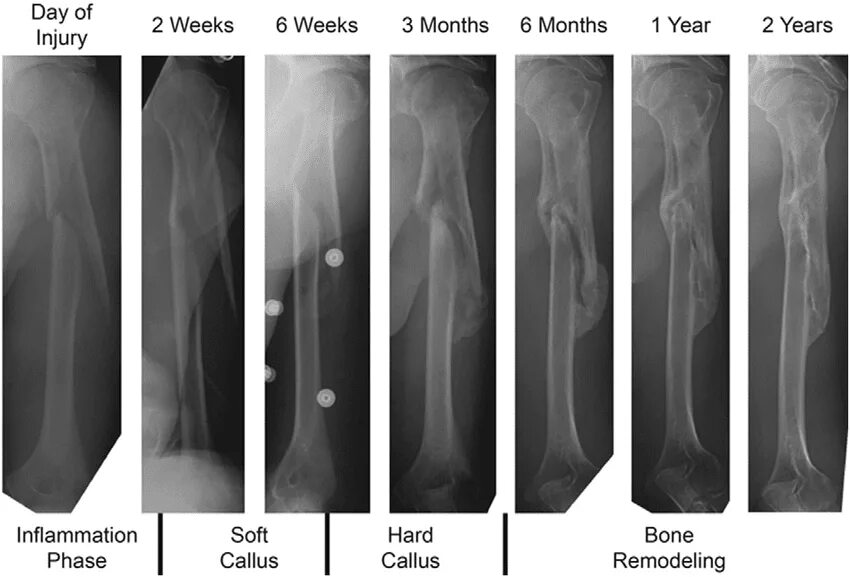

Fracture modeling